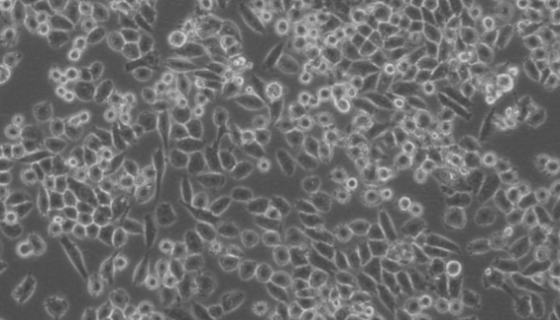

人食管鱗癌細(xì)胞的背景與應(yīng)用及培養(yǎng)操作步驟!

人食管鱗癌細(xì)胞可以用于ZNF382抑制人食管鱗癌細(xì)胞生長(zhǎng)與轉(zhuǎn)...